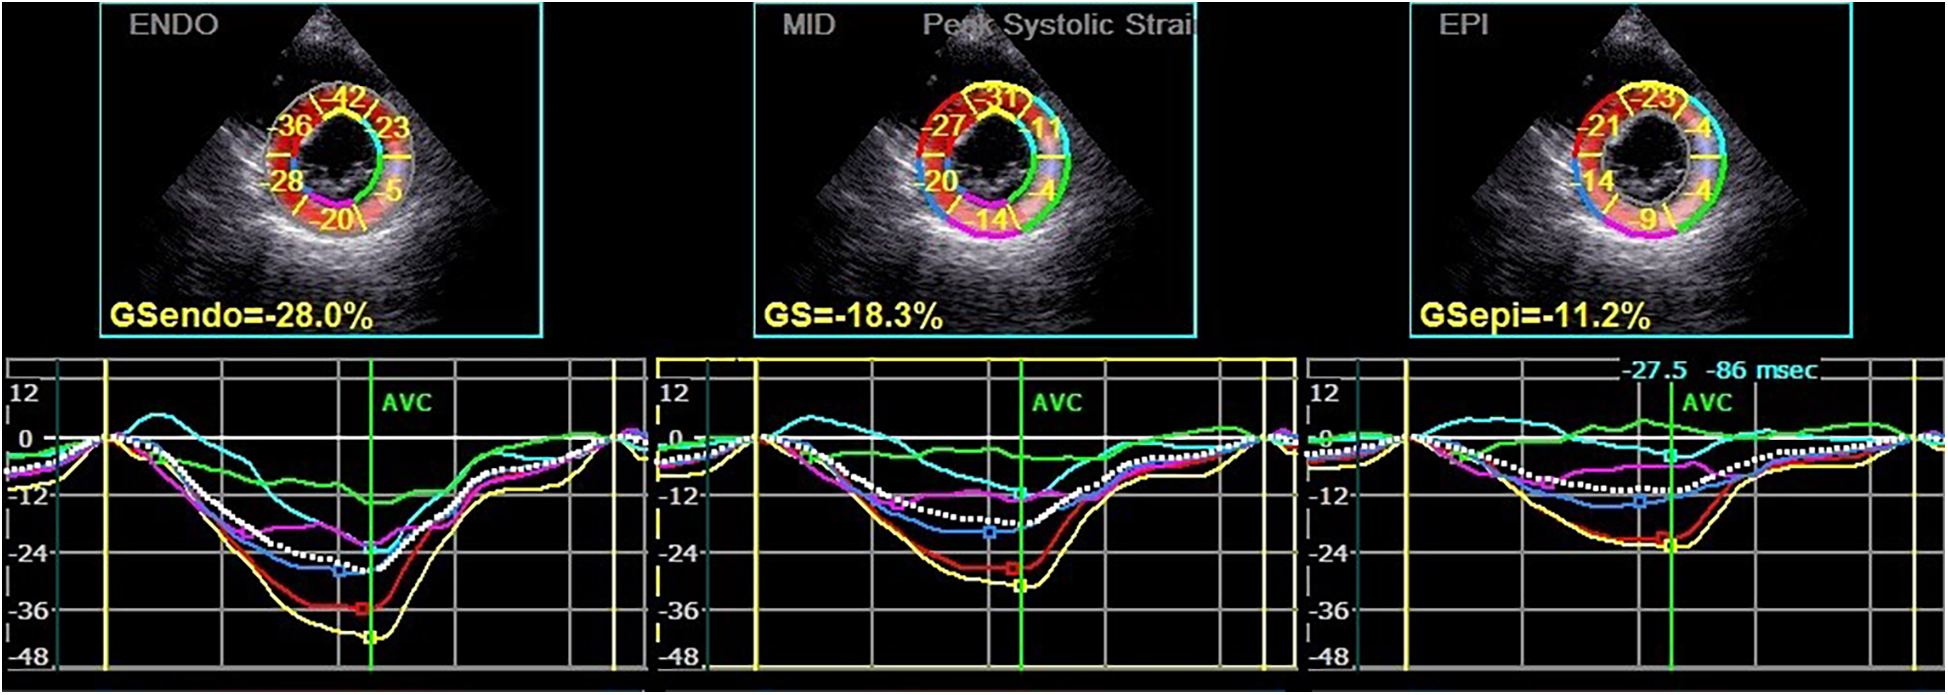

Figure 2

Circumferential strain and strain curve of the left ventricular myocardium in a hypothyroidism patient. The upper half of the picture depicts the peak systolic circumferential strain of the endocardium, mid-myocardium, and epicardium (PCS-endo, PCS-mid, and PCS-epi) values of each segment in left ventricular short-axis mitral valve level view, and the lower half shows the strain curve corresponding to each segment.

Subsequently, the stored dynamic images were Q-analyzed for 2D strain using the offline EchoPAC113 software. The endocardium of the dynamic images from six views (short-axis and long-axis of the left ventricular) was manually traced. After that, the system automatically segmented the left ventricular wall into inner, middle, and outer myocardial layers, and speckle-tracking analysis was carried out on each layer. Manual adjustment of the region of interest was permitted to ensure optimal tracking quality. The system divided each LV base segment, middle segment, and apical segment into six walls (anterior septum, anterior wall, lateral wall, posterior wall, inferior wall, and posterior septum), resulting in a total of 18 segments (1). Peak longitudinal strain (PLS), peak circumferential strain (PCS), global longitudinal strain (GLS), global circumferential strain (GCS), and the corresponding strain curves for each cardiac cycle were automatically generated (Figures 1, 2), and the relevant bull's-eye figure diagrams were displayed.